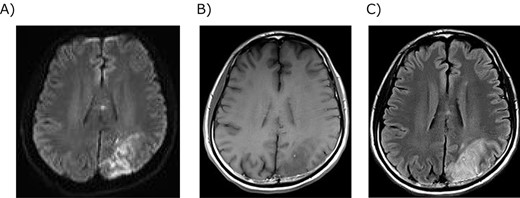

The patient required reintubation due to postoperative pneumonia and was extubated on day five. On that day, the patient complained of numbness in the little finger of his right hand, but no other neurological abnormalities were observed. The numbness was believed to be caused by nerve compression due to the patient’s posture, so the patient was followed up. On the ninth day, he was unable to write. Apraxia, such as writing and calculation, was observed, but no other symptoms were obvious. Brain magnetic resonance imaging revealed a cerebral infarction in his left parietal lobe (Fig. 3). Argatroban hydrate was administered, and the cause of cerebral infarction was investigated. No atrial fibrillation was detected during or after the surgery. Transthoracic echocardiography did not reveal a thrombus in the atrium or at the pulmonary vein stump. The computed tomography scan showed no cause of embolism on either side of the internal carotid arteries or the aortic arch. Magnetic resonance angiography showed hypoplasia of the origin of the middle cerebral artery and compensatory vascular formation (Fig. 4). The infarction was diagnosed as caused by an aplastic/twig-like middle cerebral artery (Ap/twig-like MCA). While undergoing rehabilitation, the patient completed postoperative adjuvant chemoradiotherapy after his discharge. He succeeded in returning to work six months after surgery. He has been alive without recurrence for eighteen months.

Magnetic resonance imaging of the brain infarction. (A) Diffusion-weighted image showed strong signals in the left parietal lobe. (B) T1-weighted image showed a low signal in the infarction. (C) T2-weighted image showed a high signal in the infarction.